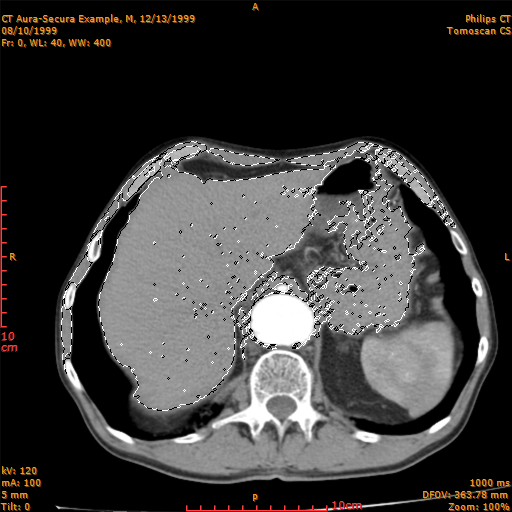

Magic Wand:

The magic wand tool lets you select a continuous area of similar intensity without having to trace its outline.

When you have selected an area with the magic wand tool and before change tool, if you modify the tolerance the selected area is modified accordingly with the new tolerance.

You can adjust the tolerance with the menu command Selection Tolerance Dialog Box of the View menu.